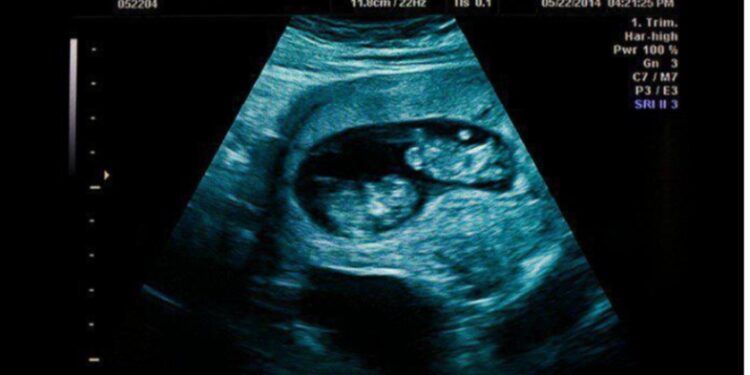

Καλησπέρα. Το όνομά μου είναι Έλσα, είμαι 30 ετών, έγκυος 11 εβδομάδων σε δίδυμα και πριν δέκα μέρες με εγκατέλειψε ο σύντροφός μου.

Η χαρά του ήταν τεράστια. Ήταν ευτυχισμένος, φρόντιζε να με προσέχει, μου θύμιζε να τρέφομαι σωστά, να μην καπνίζω, και να διατηρώ μια καλή και υγιή εγκυμοσύνη. Όταν μάθαμε πως περιμένουμε δίδυμα, ήταν ακόμα πιο ενθουσιασμένος – παρά το αρχικό σοκ.

Από την άλλη, δεν είμαι σίγουρη ότι μπορώ να αντέξω μια έκτρωση. Ακούσαμε τις καρδιές τους να χτυπούν. Ένιωσα ήδη ότι μεγαλώνουν μέσα μου δύο ζωές.